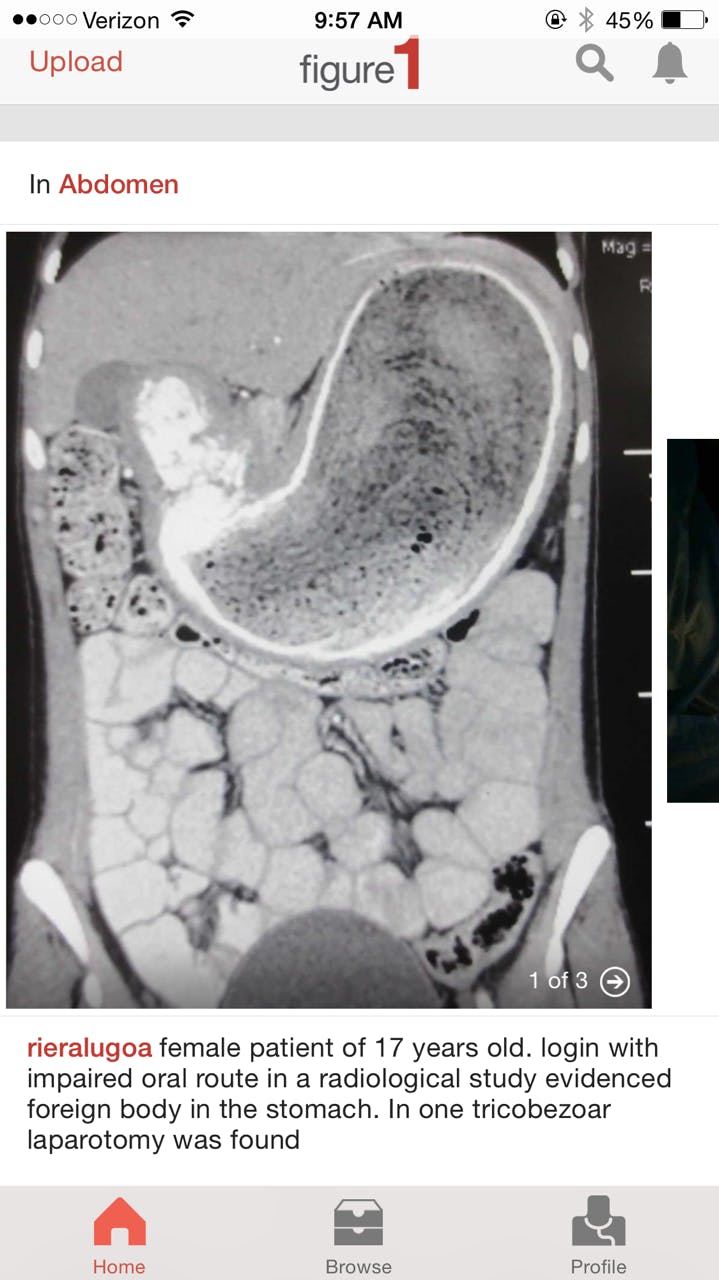

When doctors pull cool stuff out of your insides, they can show it off to the other medical professionals in the room, but there’s no easy way for them to showcase their handiwork to the global medical community. An app called Figure 1, however, makes it a snap for medical professionals to share photos of anatomical wonders with each other—and some of these photos are pretty gnarly.

Figure 1 has been around since 2013, and the podcast Reply All even devoted an episode to it last fall. But recently, non-medical professionals started using the app to satisfy their curiosity about the wonders (re: horrors) of the human body.

Users can search for pictures by location on body or by medical specialty. Whether you’re a neurologist who wants to examine abnormal brain scans, a dermatologist who wants to look at skin conditions, or just a plain ol’ weirdo, there’s something on Figure 1 for you.

The app also has a Facebook-style newsfeed of the latest photos to be uploaded to Figure 1, and those who upload the photos will often write a short appraisal of the patient’s condition.